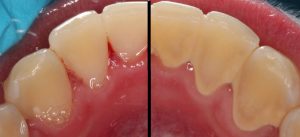

The photo below shows the lower teeth on the side facing the tongue. On the left, the teeth and gums have been professionally cleaned. Notice the whiter color and less “blocky” look compared to the photo on the right. Calculus and plaque cover the teeth on the right.

Unfortunately, it can be difficult to tell if you have calculus unless you have a severe case, like the one pictured below.